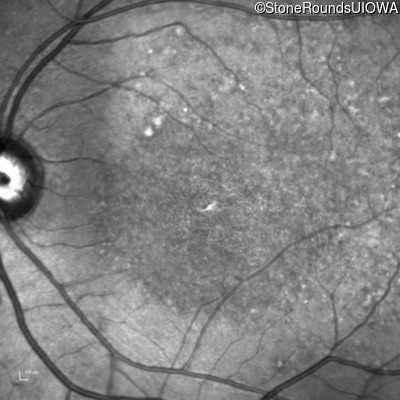

This 16 year old female first had difficulty seeing the blackboard at age 9. Her eye doctor at the time felt at the time that she was "faking it". More recently her eye doctor told her she would be blind by age 20 and suggested she get a seeing eye dog.

| AR Stargardt Disease | ABCA4 | Asp507Tyr GAT>TAT | IVS40+5 G>A | AR |